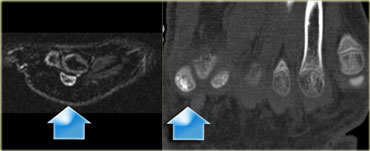

Stress fracture of sesamoid of great toe: sagittal STIR and axial CT. Stress fracture of sesamoid of great toe: sagittal STIR and axial CT.

Sesamoid bones

Sesamoid bones are uncommon sites for stress fractures.

On the left a 14-year old male soccer player with persistent plantar forefoot pain.

Stress fracture of the medial sesamoid of the great toe is indicated by a high signal intensity on an MR sagittal STIR-sequence at presentation.

A CT performed at presentation shows sclerosis of the medial sesamoid and confirms the diagnosis of stress fracture.